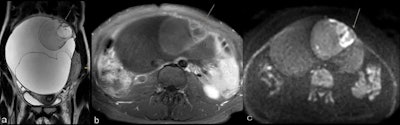

Mucinous borderline tumor and stage IA invasive ovarian cancer in a 28-year-old woman. Coronal T2 (a) demonstrates a large multilocular cystic mass of the right ovary typical of a mucinous tumor. At its superior aspect areas with irregular septations, contrast enhancement (b), and restricted diffusion (c) are demonstrated (arrow).

Mucinous borderline tumor and stage IA invasive ovarian cancer in a 28-year-old woman. Coronal T2 (a) demonstrates a large multilocular cystic mass of the right ovary typical of a mucinous tumor. At its superior aspect areas with irregular septations, contrast enhancement (b), and restricted diffusion (c) are demonstrated (arrow). Time-intensity curves of the uterus (orange) and solid tissue of the mass (blue) demonstrate type 2 curve with typical initial rise followed by a plateau. At histopathology, in this area, foci of invasive cancer were seen. Images courtesy of European Radiology.

Time-intensity curves of the uterus (orange) and solid tissue of the mass (blue) demonstrate type 2 curve with typical initial rise followed by a plateau. At histopathology, in this area, foci of invasive cancer were seen. Images courtesy of European Radiology.Early detection remains one of the unmet needs in the management of this disease. Transvaginal sonography and MRI are effective tools to characterize ovarian masses, and greater standardization of imaging technique and implementation of predictive models of risk of malignancy can contribute to better detection, Forstner added.